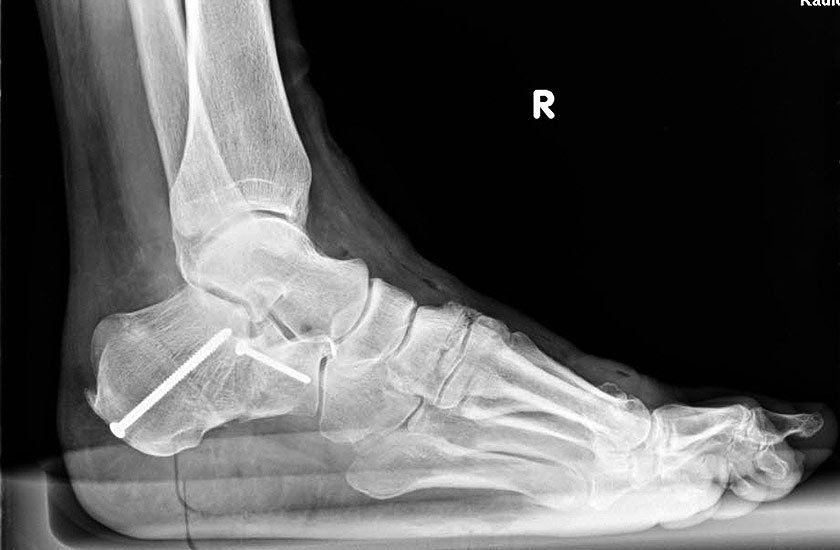

Konventionelles Röntgen

Stehende konventionelle Röntgenbilder eines Fußes mit Planovalgus Deformität Stadium II b dorsoplantar (dp) und seitlich. Auf der dp-Aufnahme zeigt sich die talo-calcaneare Divergenz, der gegenüber dem Kalkaneus nach anterior gleitende Talus und d

Stehende Aufnahmen des Fußes dorsoplantar (dp) und seitlich sowie des OSG anteroposterior (ap) sind die Grundlage der konventionellen Röntgendiagnostik (Abb. 5). Ergänzend werden gelegentlich die Rückfuβ-Alignement Aufnahme nach Saltzman 19 und Vergleichsaufnahmen der Gegenseite durchgeführt.

Der Talo-Metatarsale I Winkel bzw. die laterale talonaviculare Subluxation auf der stehenden dorsoplantaren Aufnahme des Fuβes dokumentieren das Ausmaβ des Vorfuβ abductus (Abb. 6 a,b). Ein dp Talo-Metatarsale I Winkel von > 10° (nach medial konvex) ist als pathologisch anzusehen. Mit der Bestimmung der talocalcanearen Divergenz (Abb. 6 c) erhält man ein Eindruck über das Ausmaβ des Rückfuβ valgus; eine leichte Divergenz bis ca. 12° gilt als physiologisch 20.

Auf der seitlichen, stehenden Aufnahme des Fußes wird ebenfalls der laterale Talo-Metatarsale I Winkel (Abb. 6 d) gemessen und so das kollabierte mediale Längsgewölbe dokumentiert. Auch hier gilt ein Talo-Metatarsale I Winkel von > 5° (nach plantar konvex) als pathologisch 21. Der Kollaps findet dabei meist im Talonaviculargelenk, seltener in der Naviculocuneiform-Gelenkreihe statt. Instabilität und Arthrose im 1. TMT sollten ausgeschlossen oder bei der Operationsplanung mit einbezogen werden. Weitere wichtige radiologische Messungen zur Beurteilung der Planovalgus-Statik und Progression der Deformität sind der laterale talo-calcaneare Winkel (Abb. 6 e) und der Abstand des Os cuneiforme-Unterrandes zum Untergrund (Abb. 6 f, Cuneiform height, 22. Eine anteriore Translation des Talus auf dem Kalkaneus findet man sowohl auf der ap, als auch auf der seitlichen Aufnahme des Fuβes mit Aufhebung der Cima-Linie.